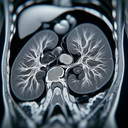

Магнітно-резонансна томографія (МРТ) нирок – це неінвазивний метод візуалізації, який використовує магнітні поля і радіохвилі для створення детальних зображень нирок та прилеглих структур. ### Показання для МРТ нирок: 1. **Аномалії розвитку**: Оцінка структурних аномалій з народження...